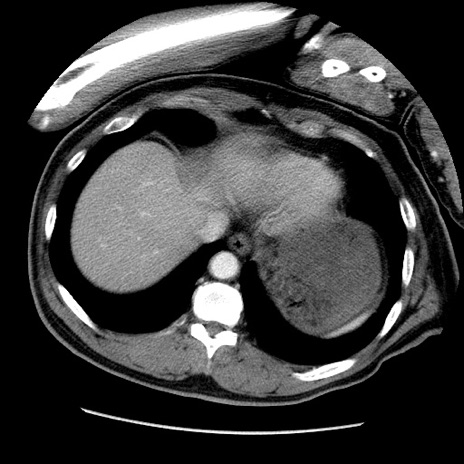

症例22(横断像)

【症例】50歳代男性

【主訴】腹痛

【現病歴】AVMからの被殻出血のため回復期リハ病棟入院中。 本日午後3時頃急に下腹部痛が出現した。

【既往歴】AVM、被殻出血、虫垂炎、高血圧

【身体所見】意識晴明、左半身不全麻痺、会話の理解は良好、36.5°C、腹部:膨隆、全体に板状硬、下腹部正中に圧痛点あり、反跳痛-、筋性防御不明、右下腹部にope scar

【データ】WBC 9400、CRP 0.06